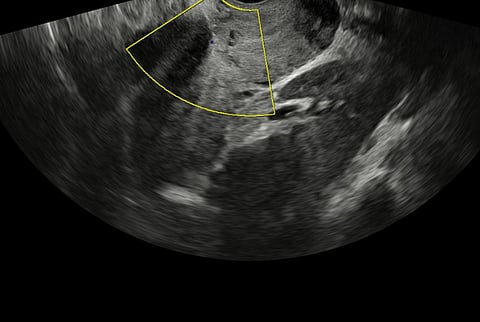

نجح مستشفى المانع العام بالدمام في إنقاذ حياة أم وجنينها بعد التعامل مع واحدة من أخطر حالات الحمل والولادة، والمتمثلة في المشيمة المنزاحة المصحوبة بالتصاق المشيمة، وهي حالة تُعد من أعلى حالات التوليد خطورة لما تحمله من احتمالية نزيف حاد قد يهدد حياة الأم.

وتعود تفاصيل الحالة إلى سيدة تبلغ من العمر 36 عامًا في الأسبوع الخامس والثلاثين من الحمل، حيث جرى تشخيص الحالة بدقة خلال فترة المتابعة الطبية، ووُضعت خطة علاجية مسبقة شاملة، تضمنت تجهيز فريق طبي متعدد التخصصات واختيار التوقيت والمكان الأنسب للتدخل، بما يضمن أعلى درجات السلامة للأم والجنين.

وأوضح الدكتور أحمد السايح، استشاري أمراض النساء والتوليد، أن التعامل مع مثل هذه الحالات يتطلب تشخيصًا مبكرًا وتخطيطًا دقيقًا، مشيرًا إلى أن الفريق الطبي قام بتجهيز الحالة قبل العملية للحد من النزيف المتوقع، تلاه إجراء ولادة قيصرية مخططة في ظروف طبية مسيطر عليها بالكامل، مع استئصال الرحم القيصري بخطوات دقيقة.